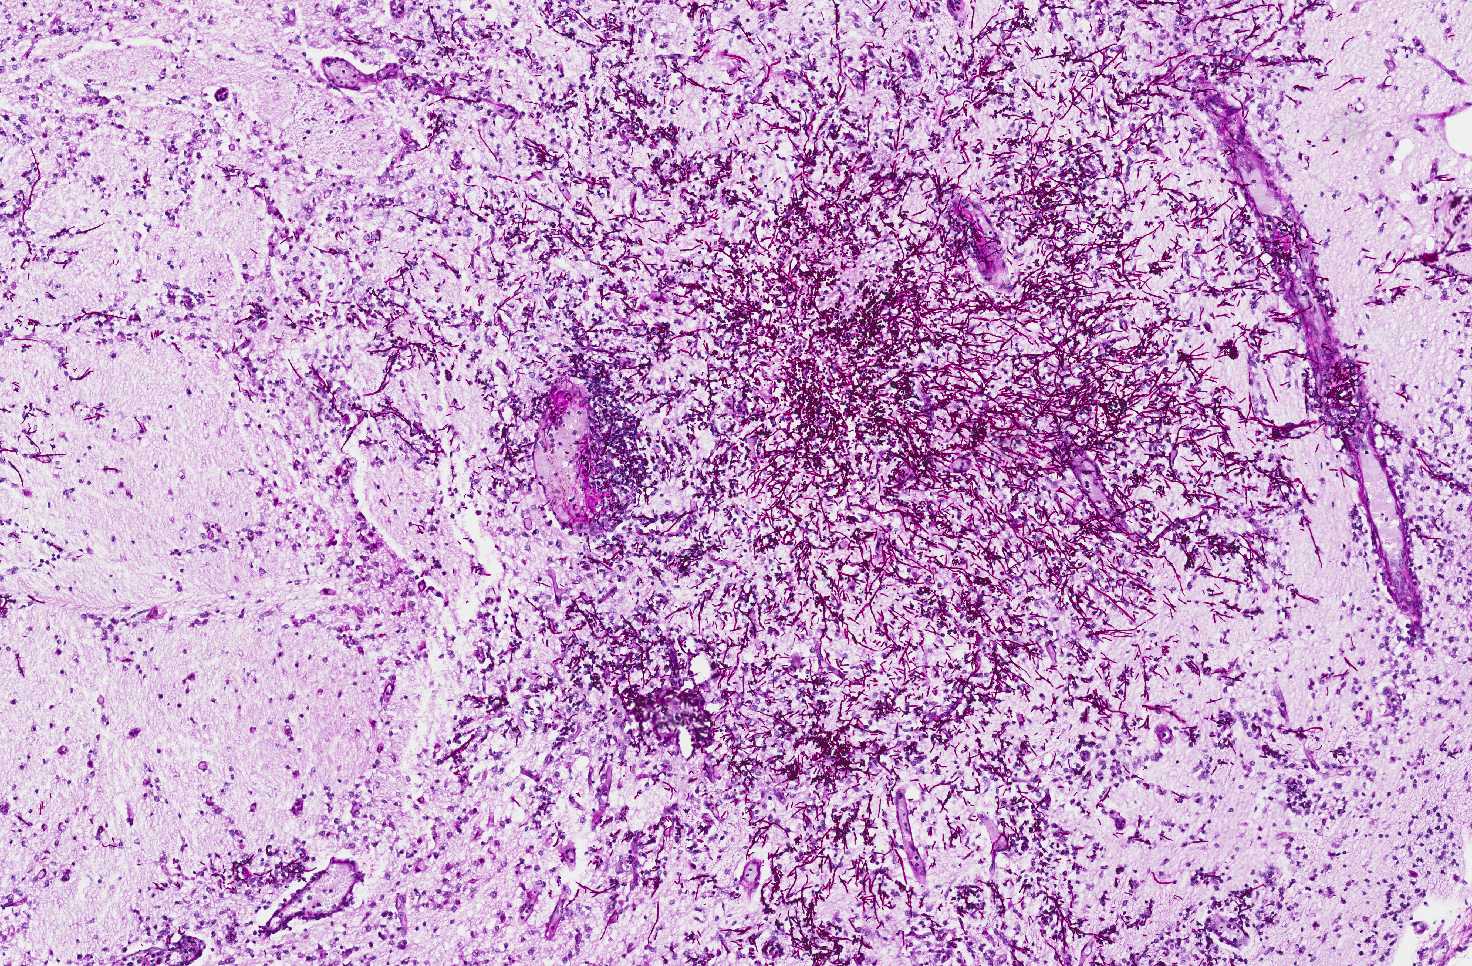

PAS Stain

Area 3: Numerous hyphae are demonstrated by PAS stain.

• In areas with more intense inflammatory cell infiltration (Area 2 and 3), numerous fungal hyphae are present.